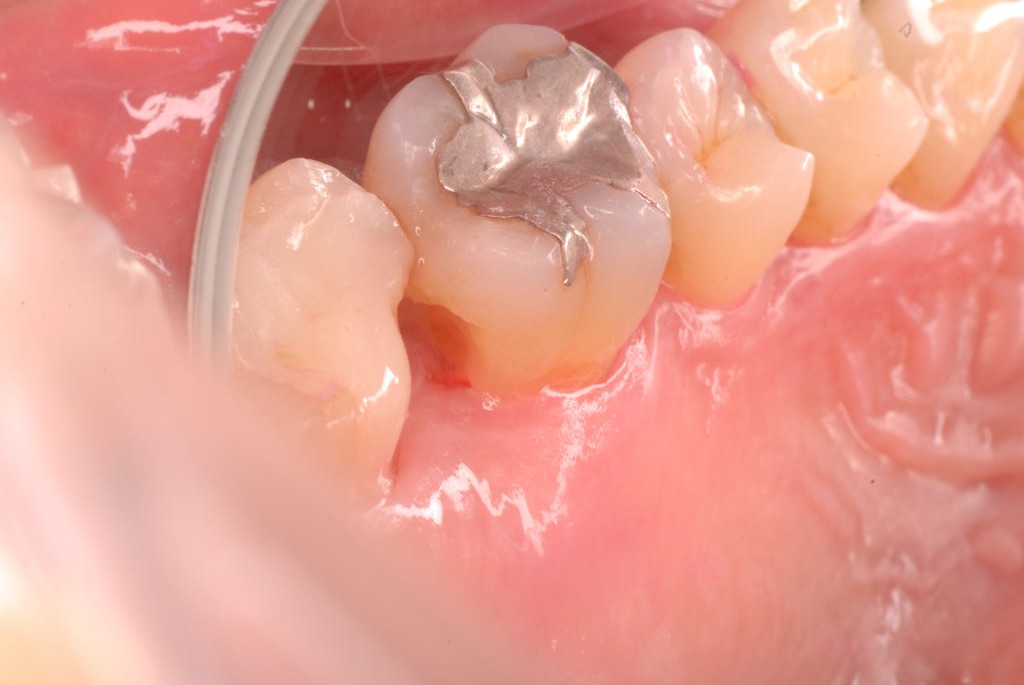

ご自分でやられても歯茎から血が出ないと話をされていましたが、私がブラシを当てると悲惨な状態であることがわかりました。

何故歯が悪くなるのか、歯周病で抜けるのか分からなければ何を入れても歯は悪くなり抜けていくのです。

病気を治しましょう。それから差し歯や入れ歯を入れましょう!物を入れれば入れるほど、磨き方や掃除の仕方が上手にならなければ、すぐ抜けてくるのです。